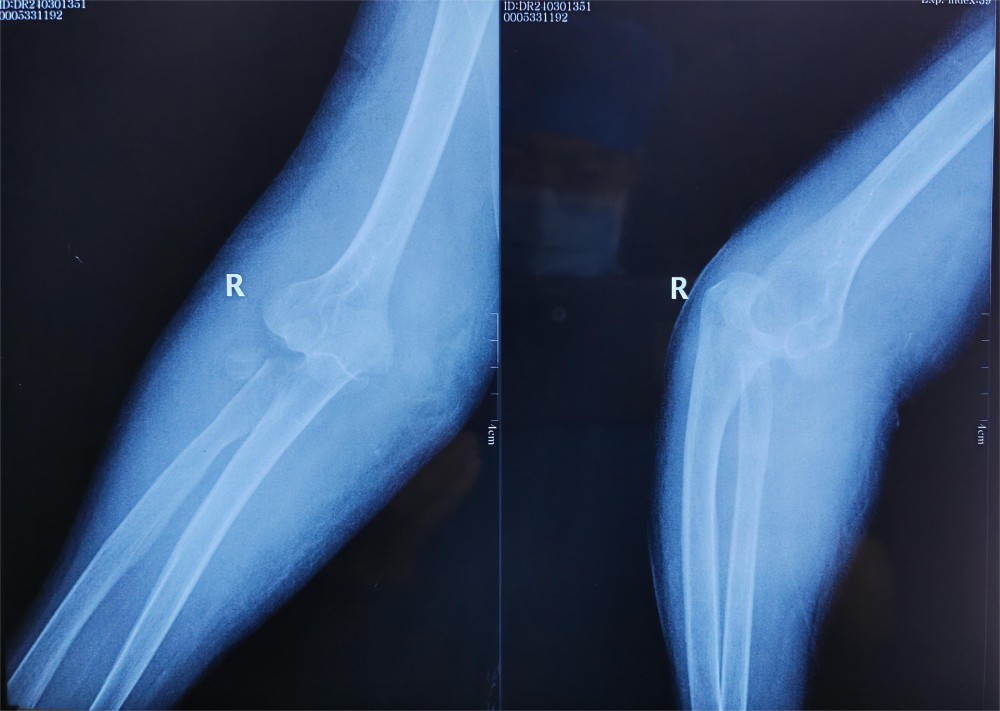

患者徐某,76岁,右肘部疼痛肿胀伴活动受限1天入院,患者于入院前1天,不慎被车从后侧撞伤,伤及右肘部,当时即感右肘部疼痛、畸形伴活动受限。受伤时患者否认头痛、头晕,胸闷、气短,恶心、呕吐等不适,被人救起后即赴某三甲医院就诊,行X光片检查显示:右肘关节脱位,右尺骨冠状突骨折,右桡骨头粉碎性骨折(肘关节恐怖三联征),给予手法复位肘关节脱位,患者为求进一步诊治赴91直播 门诊就诊,门诊以“1.右桡骨头粉碎性骨折2.右尺骨冠状突骨折”,收入91直播 创伤外科中心A区。